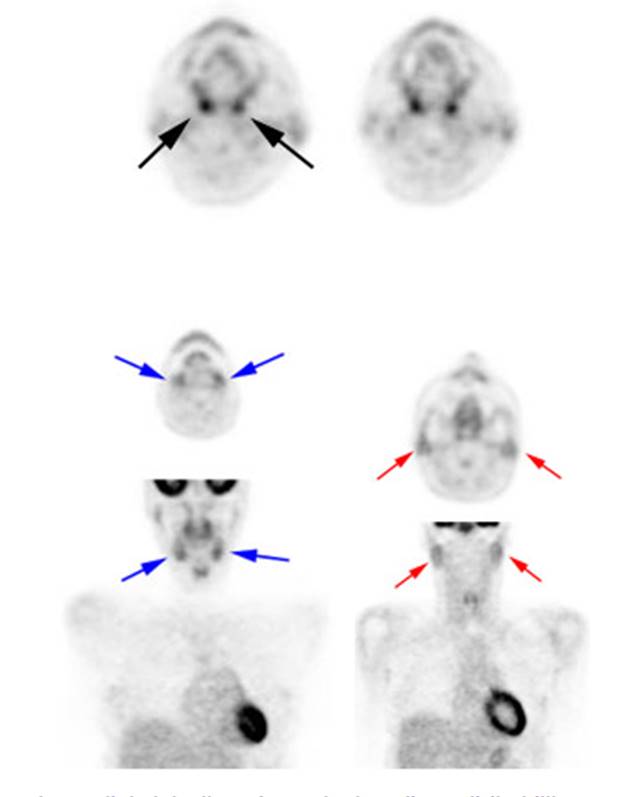

o

Low to moderate FDG uptake occurs in the lingual

and palatine tonsils and at the base of the tongue because of physiologic

activity associated with the lymphatic tissue in Waldeyer's

Figure 3 - Head and neck activity: The images below show

typical uptake in the tonsils (black arrows), submandibular glands (blue arrows),

and parotid glands (red arrows)